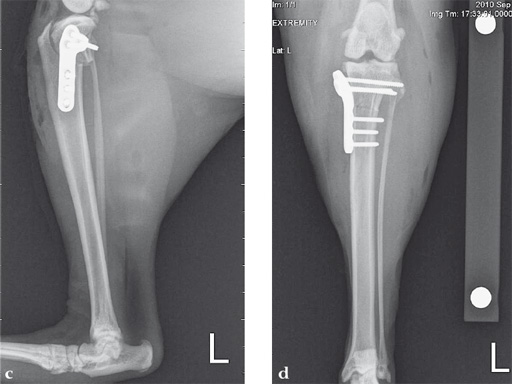

Case 1: Cocker Spaniel

(Case provided by Brian Beale, Houston, USA)

An 11-year-old female, spayed, 13.6 kg cocker spaniel had a complete tear of the left cranial cruciate ligament. A 2.4 mm TPLO plate was perfect for this dog due to the excessive slope of the tibial plateau (30) and the size of the dog. Three 2.4 mm locking screws were used proximally and three 2.4 mm cortical screws were used distally. The contour of this plate matches the contour of the bone almost perfectly. The plate is also designed to optimize the angle of the proximal screws so that they engage the most dense and thickest bone and avoids penetration of the stifle joint.